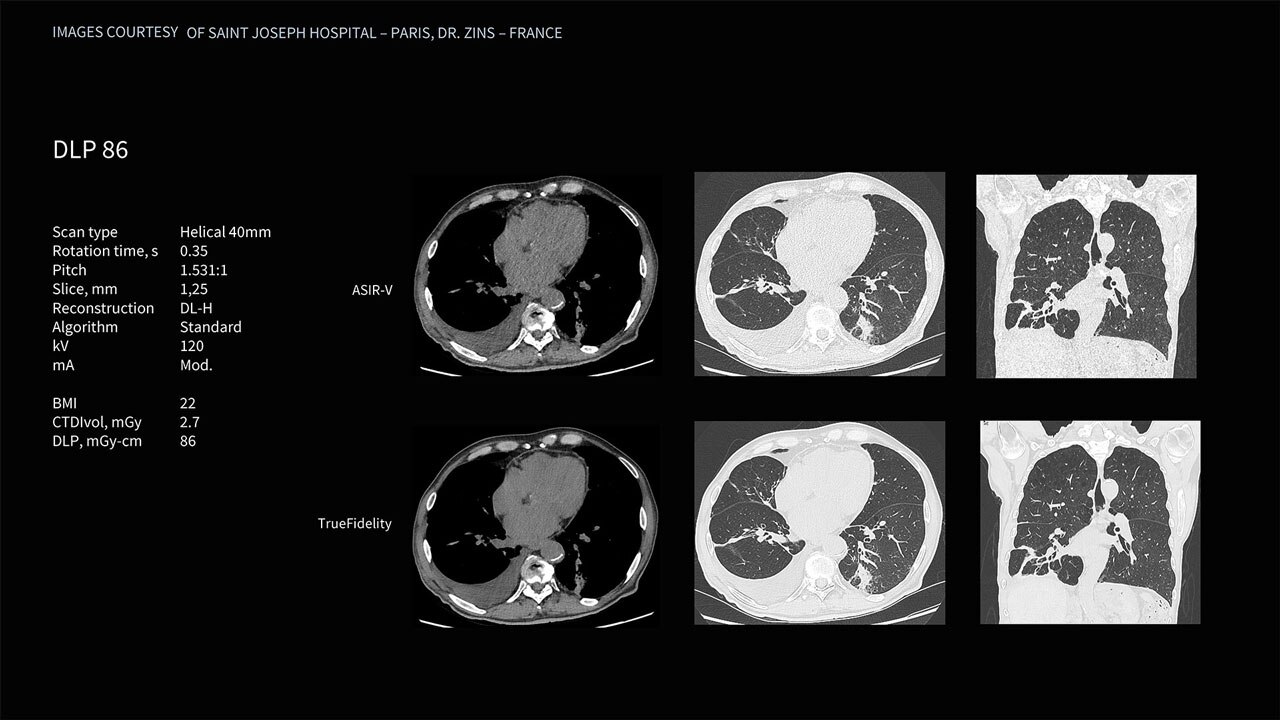

Deep learning image reconstruction, higher special resolution at 0.23 mm